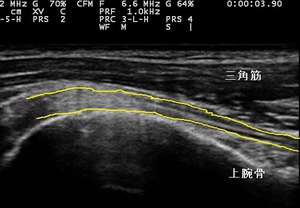

右上腕二頭筋長頭腱 超音波長軸像 左同部 正常(健)側

1週間経過後も痛みが引かず、腕も挙がらない為、当接骨院を受診されました。超音波観察において右上腕二頭筋

長頭腱(左右上画像の黄色線)に部分的な断裂が認められました(左上画像の矢印)。また、部分断裂部周辺で

炎症反応の血流増生も認められました(左上画像の矢頭)。